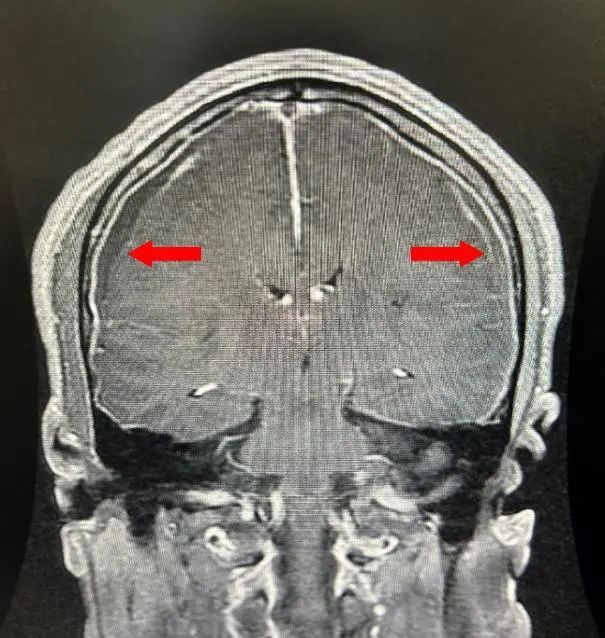

术后第3天,老俞就出院继续回家躺着去了。术后2周,老俞把CT结果发给应广宇,可以看到,硬膜下的积血已被显著吸收,侧脑室也较前有增大,这说明颅内压力已趋向于正常,可以尝试下床活动了。